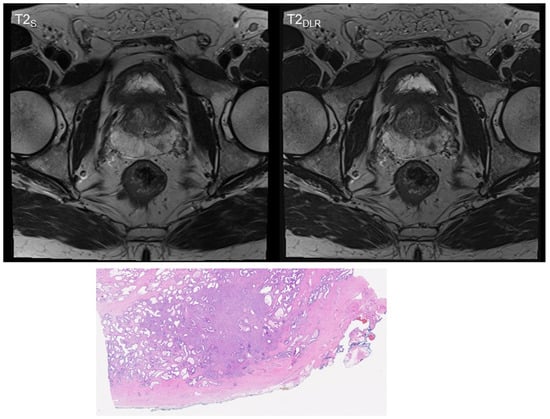

3.1. Image Quality Analysis

3.2. T2 and PI-RADS Scoring and Lesion Size Measurement

| T2S | Standard T2-weighted TSE imaging; |

| T2DLR | Deep learning reconstructed T2-weighted TSE imaging; |